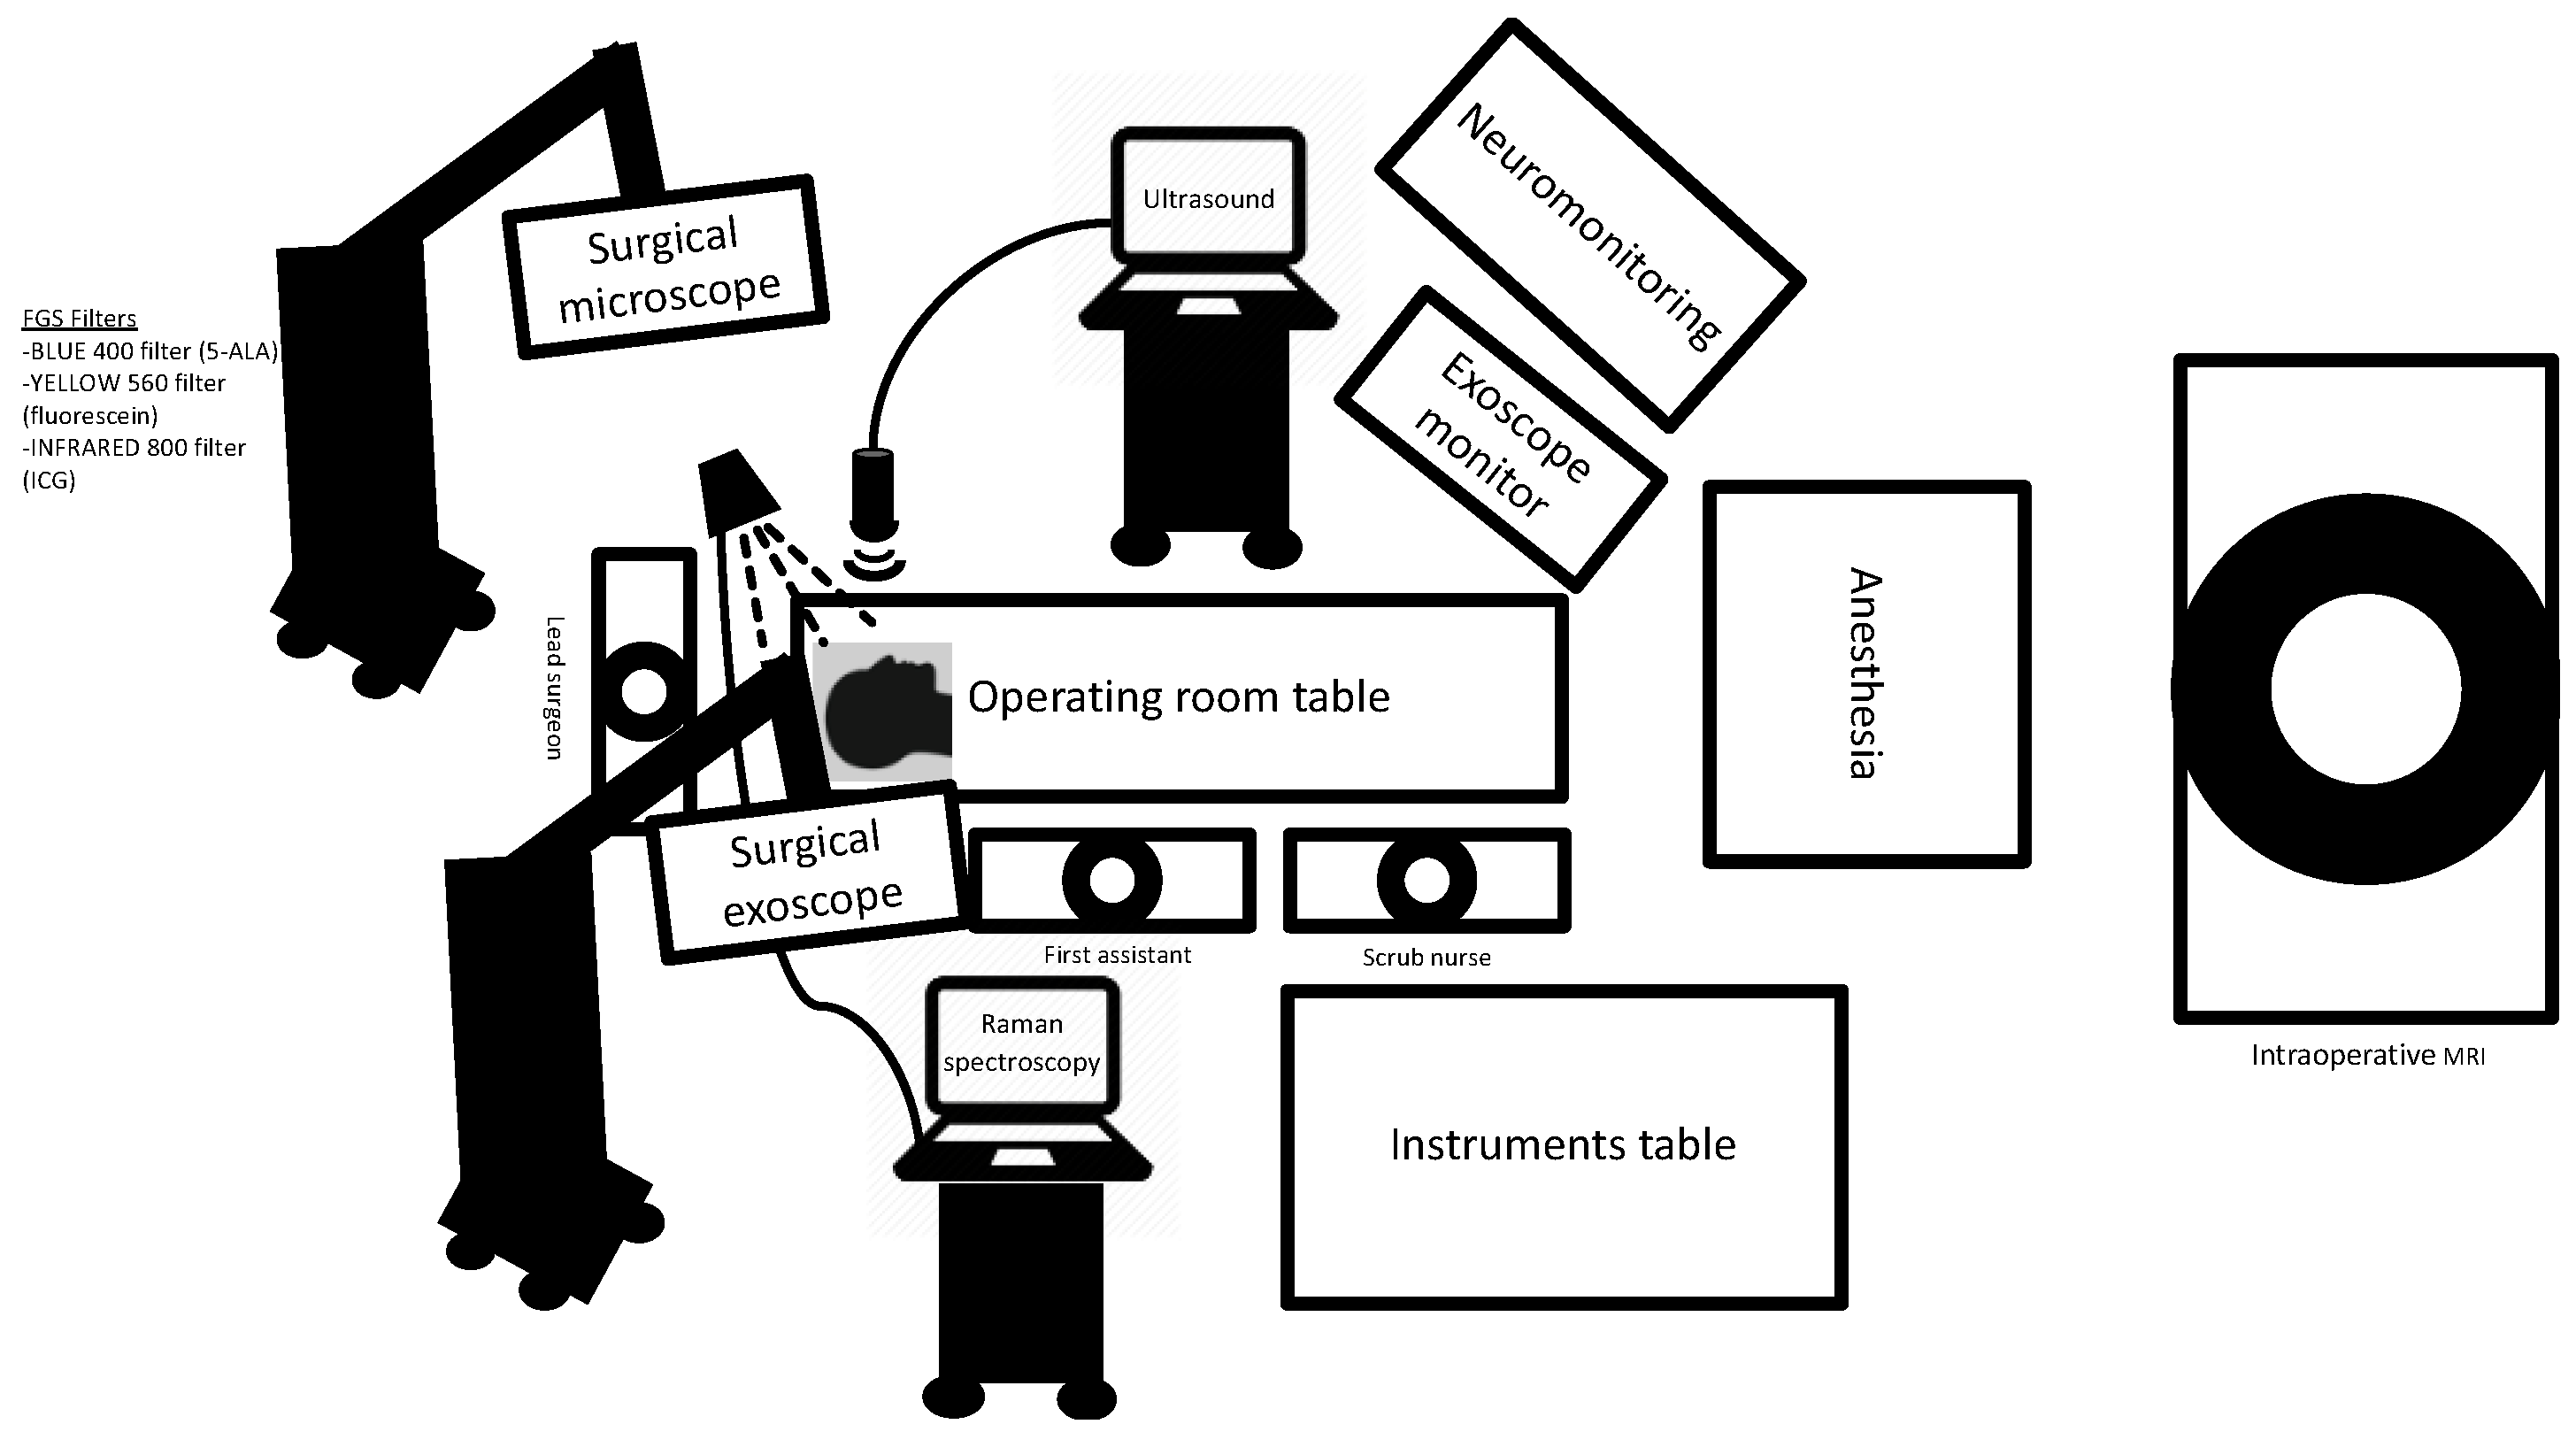

2. Fluorescence-Guided Surgery (FGS)

3. Image Guidance

3.1. Neuronavigation

3.2. Intraoperative MRI

3.4. Exoscope

3.5. Intraoperative Ultrasound

3.6. Intraoperative Mapping and Neuromonitoring

3.8. Raman Microscopy

3.8.1. Probe-Based Microscopy